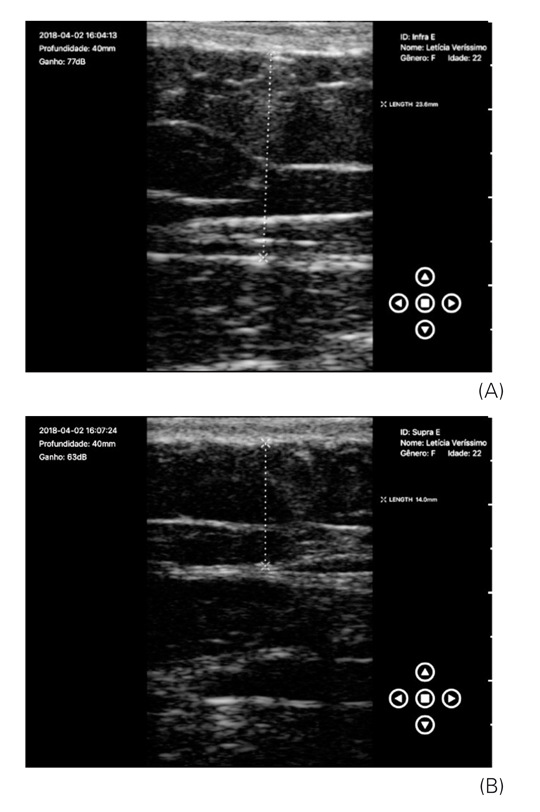

Verificou-se que, no momento inicial nas avaliações das medidas supra e infraumbilical, já existia uma diferença, fato que dificultou a interpretação dos resultados na avaliação final, quando também se observou uma diferença entre as zonas supra e infraumbilical esquerda. Mas ao analisar as imagens de ultrassonografia individualmente, é possível perceber a diferença entre as regiões tratadas e controle, conforme demonstra as Figuras 3A e 3B (análises ultrassonográficas da região infra e supraumbilical esquerda antes do tratamento), Figuras 4A e 4B (análises ultrassonográficas da região infra e supraumbilical direita, controle), Figuras 5A e 5B (análises ultrassonográficas da região infra e supraumbilical esquerda após tratamento) e Figuras 6A e 6B (análises ultrassonográficas da região infra e supraumbilical direita após tratamento, controle).

(A) Análise ultrassonográfica da região infraumbilical esquerda, 2,36 cm; (B) Análise ultrassonográfica da região supraumbilical esquerda antes do tratamento, 1,40 cm

Os autores.

Por meio das imagens de ultrassonografia demonstradas nas Figuras 3 e 5 e dos dados contidos na Tabela 2, verificou-se que a região tratada teve uma redução importante, comparada com a do lado controle, de 0,6 cm na região infraumbilical e 0,15 cm na região supraumbilical. Do total da amostra, 21 mulheres apresentaram esse comportamento, assim a diferença sempre foi mais acentuada na região infraumbilical, na qual o aplicador da TOC foi utilizado de forma estacionária. Mas no lado controle, percebeu-se que a região infraumbilical não se alterou após o período de quatro semanas e na região supraumbilical a redução foi 0,14 cm, em uma voluntária. Em seis participantes, a região supraumbilical não apresentou redução. Não foram feitas análises em quatro mulheres, pois estas não realizaram o exame final. A análise foi feita pela avaliação do ultrassonografista.